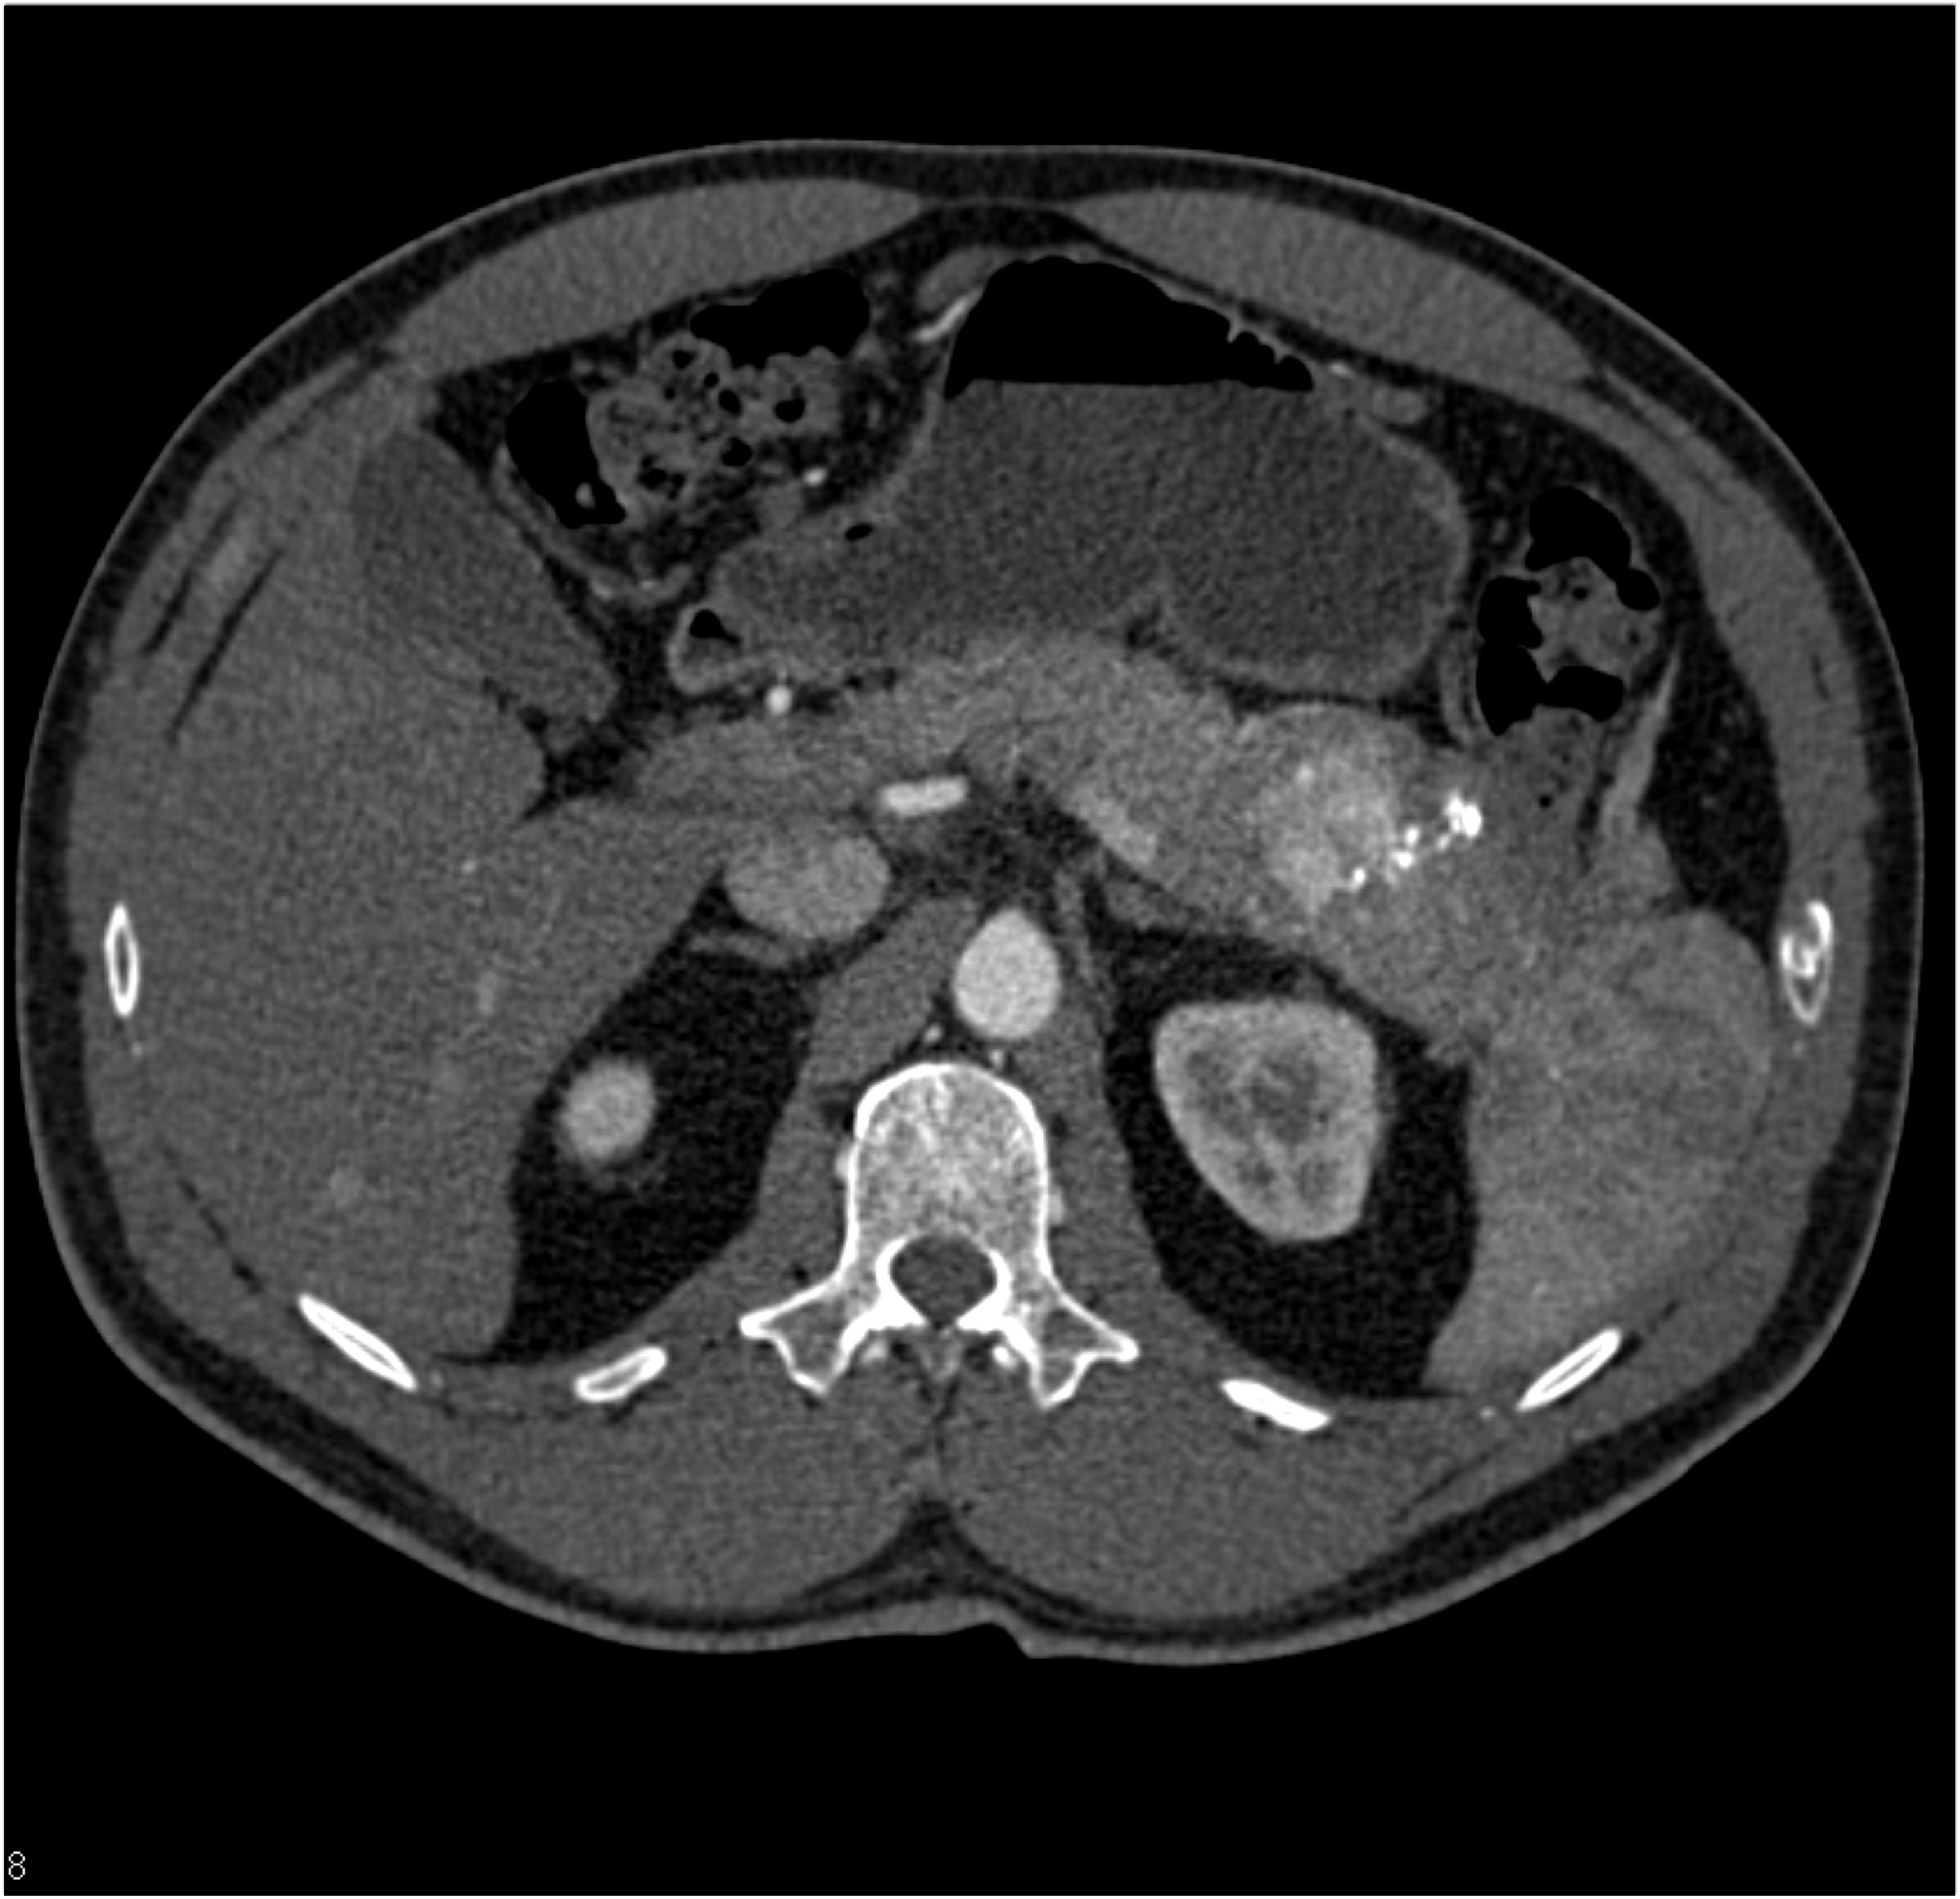

5) The most likely diagnosis in this patient with weight loss is?

lymphoma

adenocarcinoma

GIST tumor

carcinoid tumor